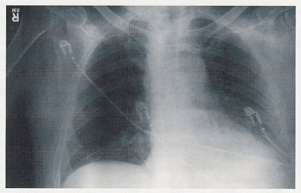

Inhalational anthrax results from __

The initial presentation of inhalational anthrax is characterized by __

A key feature of inhalational anthrax is __

Inhalation of spores

Initial presentation of inhalational anthrax: non specific, flu like symptoms

Later on: widened mediastinum on imaging

Terminal inhalational anthrax can progress to __ and can lead to death

Hemorrhagic mediastinitis/pleural effusion >> sepsis >> shock